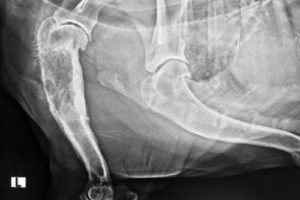

- Osteosarcoma – A highly aggressive form of bone cancer.

Osteosarcoma and Growth Hormones

Large and giant breeds that experience rapid growth in their early years may be at a higher risk of developing osteosarcoma.

Growth hormones and rapid bone development are thought to contribute to this aggressive cancer.

- Lameness or swelling in the limbs